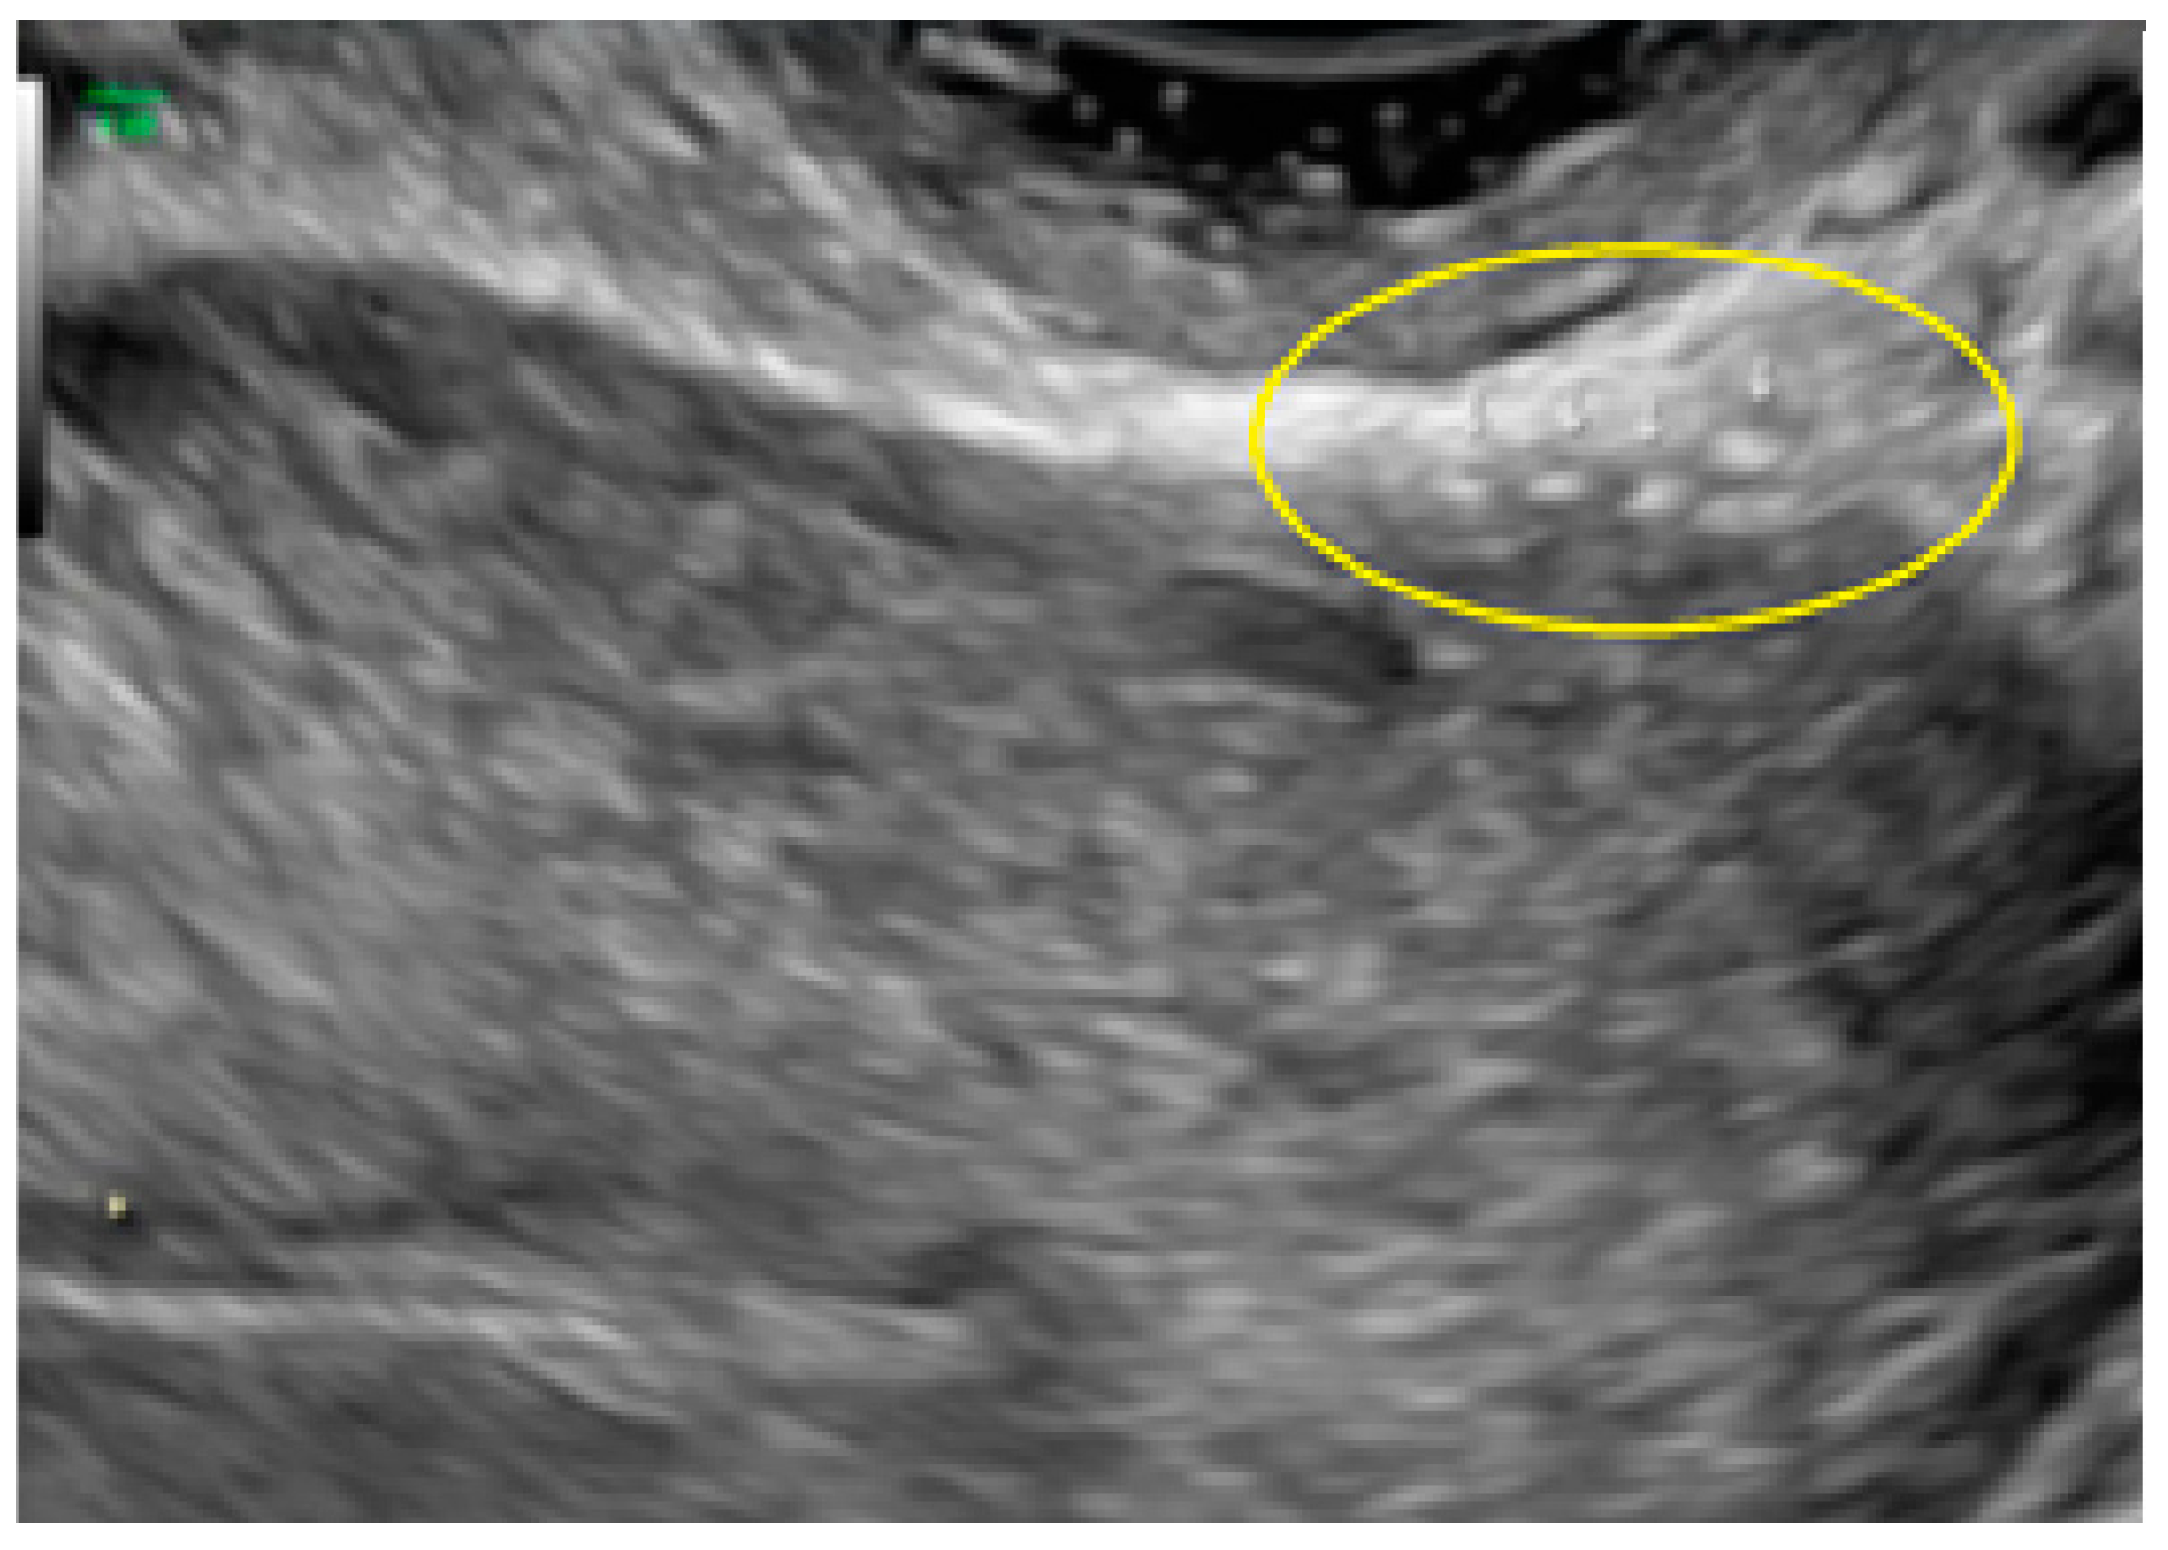

- The presence of hyperechoic foci (we called this a “pearl”).